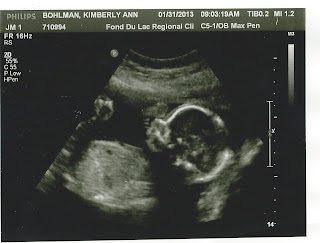

We had our ultrasound today to check on Peanut's growth and development.  Patrick and the twins came with us, so it was a busy room.  Peanut is looking good and developing right on track.  The tech check the spine, heart, kidneys and other body parts.  She didn't look at the boy/girl parts since we don't want to know.  Michael thinks he "saw something" when she was measuring the leg bones but I didn't see anything.

We had a hard time getting a good profile of Peanut because of his position and the fact that he had his arms and hands up by his face most of the time.   You can see three of the fingers by Peanuts mouth in the first picture and the arms by Peanut's face in the second one.  Only about 20 more weeks or 131 days to go.